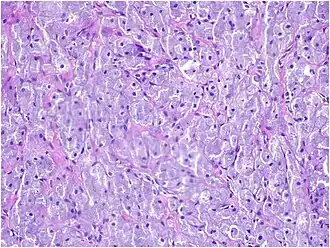

Histopathological Characteristics

Histopathologically, congenital epulis is usually characterized by the presence of big, rounded cells that fill the mucosa's lamina propria and have round to oval nuclei and an abundance of eosinophilic cytoplasm.[10] A thin layer of connective tissue separated the surface layer of cells from the growing new cells. Numerous histological traits, such as a fibrous and granulomatous appearance, have been reported in recent research.[10]

Microscopically, congenital epulis is composed of:

- Sheets of proliferating polygonal to round cells with overlying thin squamous, eosinophilic, granular cytoplasm[12][13]

- Centrally located, round nuclei [7]

These histopathological features are essential in distinguishing congenital epulis from other gingival and soft tissue neoplasms.